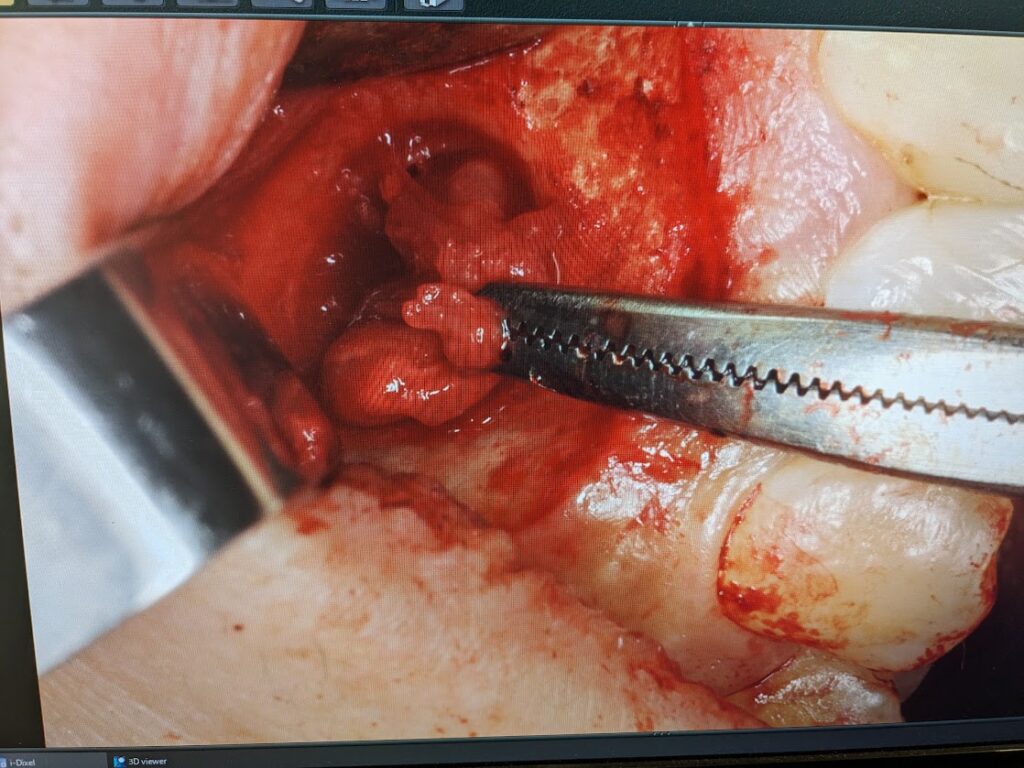

歯肉退縮を避けるように切開線を設定して歯肉粘膜骨膜弁を剥離していきますと骨膜と癒着した嚢胞壁が認められました。骨膜と癒着した嚢胞壁をできるだけ丁寧に剥離していきます。マイクロスコープを使用しますと裸眼で手術するより骨膜と嚢胞壁の堺目が良く分かります。

骨膜と分離した嚢胞を明示します。今度は骨内にある嚢胞をできるだけ一塊に摘出していきます。

嚢胞壁は菲薄化した部分が裂けると中の膿が排出されるため縮小します。